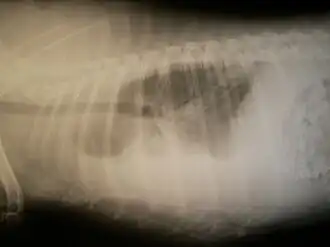

Hémothorax chez un animal.

Image d'hémothorax.